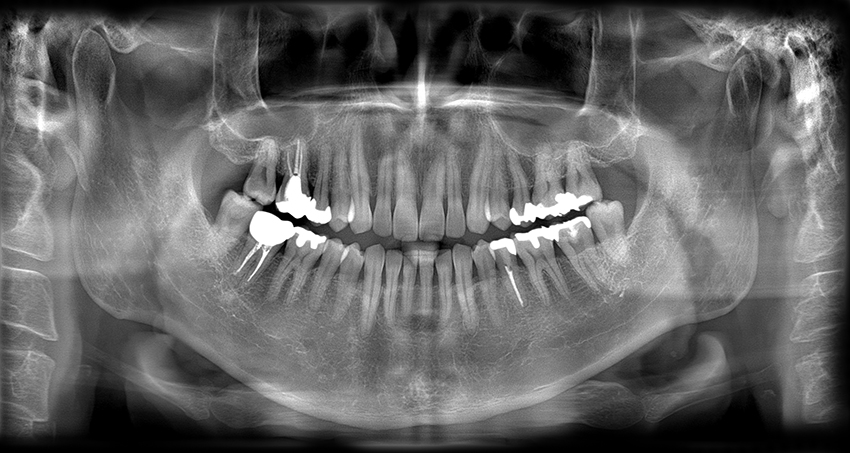

Unidad de Imagenologia Dental 3D

Poseemos Unidad Propia de Panorámicas y Estudios Cefalométricos lo cual nos brinda mayor efectividad al momento del diagnóstico y atención a nuestros pacientes.